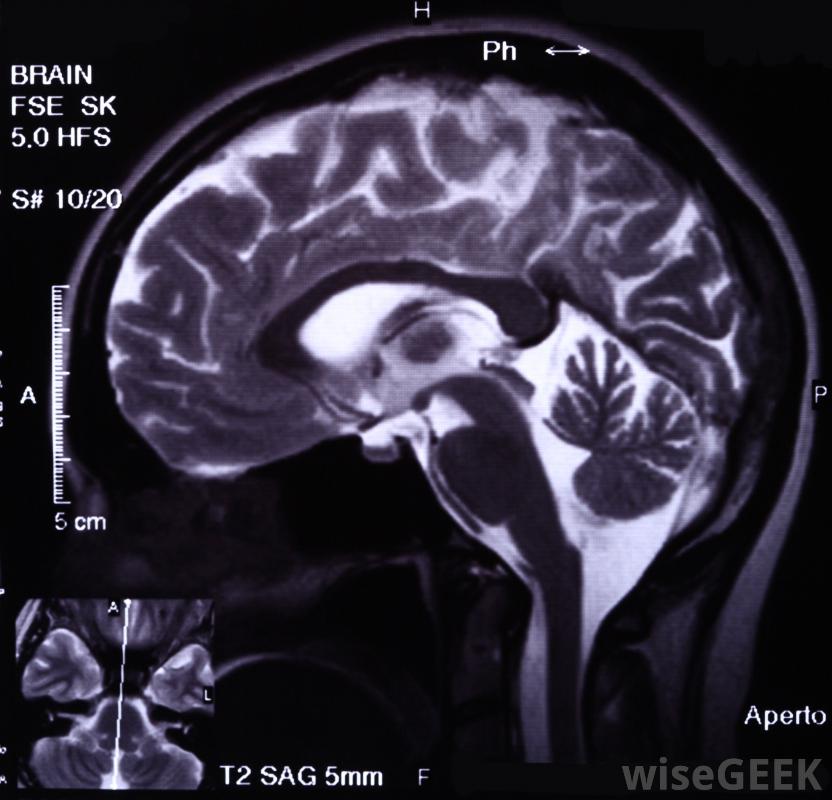

CAT扫描可用于识别大脑中可能干扰大脑功能的肿瘤从20世纪初X光机的发展开始,到20世纪60、70年代,X光机的发展开始了对人体内部的成像能力的突飞猛进,新的成像技术不断发展,随着使用这项技术的新方法,神经影像学领域从成像技术的进步中受益匪浅,这使得公司能够开发出能够探测大脑复杂情况的机器核磁共振成像技术可以生成大脑不同部位活动时发光的图像,有两种类型的神经成像:功能性和结构性神经影像学专注于大脑的功能,使用可以记录大脑活动的设备在一个典型的功能性神经成像的例子中,功能性磁共振成像(MRI)可以生成大脑不同部分活动时发光的图像。结构神经成像是静态的,与大脑的物理结构有关。例如,计算机轴向断层扫描(CAT)可用于识别脑内的肿瘤会干扰功能。

神经影像学可以用来诊断许多脑部和中枢神经系统的问题除了核磁共振成像和计算机断层扫描,神经成像还可以使用正电子发射地形图(PET)、脑磁图(MEG)、漫反射光学成像和与事件相关的光学成像技术。所有这些技术都可以用多种方式来观察大脑并了解其工作原理,有时在对比染料的帮助下,对患者的物理提示,以及其他工具,这些工具将形成更完整的大脑图像。